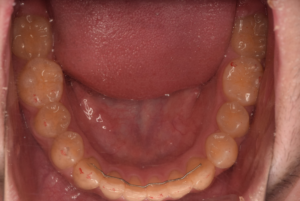

3、臼歯交叉咬合(すれ違い咬合)

・乳歯列期から治療を開始することをおすすめします。

指しゃぶりや口呼吸などによって上顎の歯列が通常に比べて狭くなっている場合、臼歯部の交叉咬合(すれ違い咬合)を引き起こすことがあります。

特に、上下正中線(前歯の真ん中のライン)が顔の真ん中のラインからずれていたり、顎が側方に偏って曲がったようになっている状態の交差咬合の場合、自然に治ることはありません。

骨格性の下顎前突と同じように、成長とともに下顎がさらに偏った状態で発育し、放っておいても症状はどんどん悪化していってしまいます。

そしてそのような交叉咬合は、歯列の変形や顎の不均衡な発育などから顔の変形(非対称)をきたし、将来、顎関節症や顎機能異常の原因となる可能性があります。

乳歯列期は上顎歯列を拡大して正常な顎やお口周りの筋肉の成長発育を促す良い時期でもありますので、この時期に治療をされることが望ましいとされています。

上顎急速拡大を3回行い鼻腔通気が改善しました。

咀嚼指導により、正中が合い、咬み合わせが安定しています。